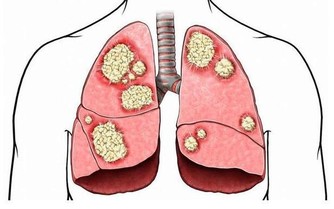

癌症的發生與自由基(Free Radicals)對細胞的損害密切相關,而綠茶中的**兒茶素(EGCG)**具有強大的抗氧化能力,可以幫助人體清除自由基,減少細胞突變的風險。

- 降低腫瘤生長:綠茶中的兒茶素可抑制癌細胞增殖,特別是在乳腺癌、前列腺癌、結腸癌方面,有一定保護作用。

- 幫助DNA修復:綠茶的多酚能夠減少DNA受損,防止基因突變導致的癌細胞生成。